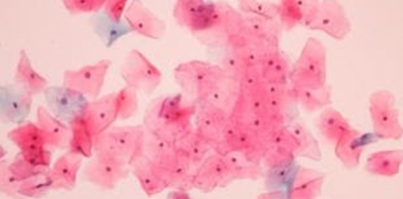

A garantia de um esfregaço satisfatório para avaliação oncótica implica na presença de células em quantidade representativa, sua distribuição e fixação.

Desde 1928, quando o médico grego George G. Papanicolaou publicou seu primeiro trabalho utilizando esfregaços cérvico vaginais para o diagnóstico de câncer de colo uterino, o exame citopatológico continua sendo a estratégia mais adotada para o rastreamento desta doença (WHO, 2010).